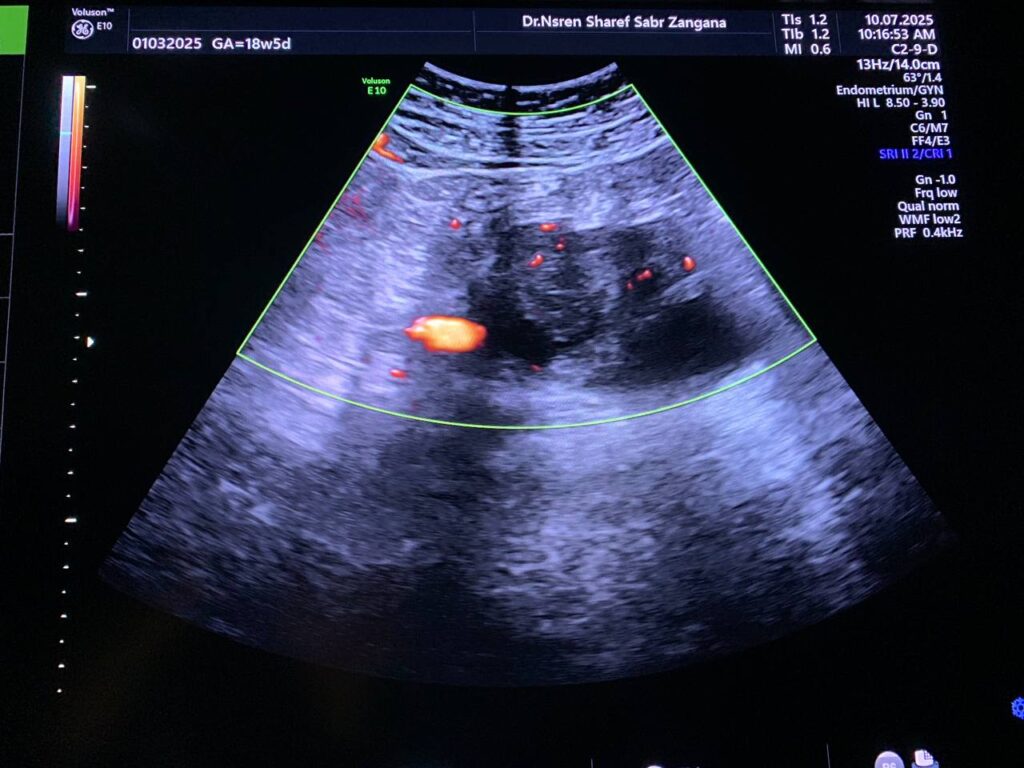

Pelvic Ultrasound

· Left ovarian solid mass vascular on color doppler score 2-3 , its size 57x48mm, no ascites , no enlarged lymph node seen, picture mostly ovarian tumor , please for further study.